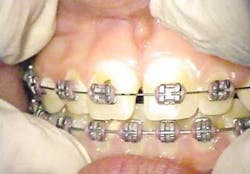

The following is a case report of one such procedure using the Opus Duo, a dual Er:YAG and CO2 dental laser system. This case begins with the diagnosis of a frenal attachment connected to the interdental papilla between maxillary central incisors (No. 8 and No. 9). The muscle attachment is bulky, and would inhibit further orthodontic correction. This patient was referred by her orthodontist for a minimally invasive laser frenectomy procedure before the next stage in her orthodontic treatment (figure 1).

After infiltration of 1cc of local anesthetic solution, the Er:YAG laser (OpusDuo, OpusDent USA) was used at 350mj with a 1,000-micron, contact sapphire tip and heavy water spray to gently ablate the frenal attachment and underlying muscle tissue down to the level of the periosteum (figures 2, 3, and 4). Once this is accomplished, there is a small defect in the vestibular mucosa and interdental papilla where the frenal attachment and muscle once was. There is no charring, no burned tissue, and free bleeding in the site (figure 5).